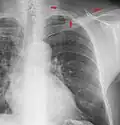

Cavities

A cavity is a walled hollow structure within the lungs. Diagnosis is aided by noting:

- wall thickness

- wall outline

- changes in the surrounding lung

The causes include:

- cancer

- infarct (usually from a pulmonary embolus)

- infection: e.g., Staphylococcus aureus, tuberculosis, Gram negative bacteria (especially Klebsiella pneumoniae), anaerobic bacteria, and fungus

- Granulomatosis with polyangiitis